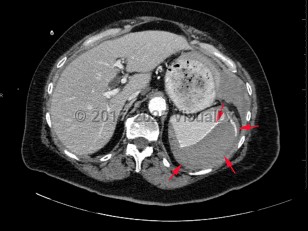

The American Association for the Surgery of Trauma (AAST) has a spleen injury grading system based on imaging and intraoperative findings:

- Grade I: subcapsular hematoma < 10% of surface area; capsular tear; parenchymal laceration < 1 cm depth.

- Grade II: subcapsular hematoma 10%-50% of surface area; parenchymal laceration 1-3 cm in depth that does not involve a trabecular vessel.

- Grade III: subcapsular hematoma > 50% of surface area or expanding ruptured subcapsular or intraparenchymal hematoma; intraparenchymal hematoma > 5 cm in diameter or expanding; parenchymal laceration > 3 cm in depth or involving trabecular vessels.

- Grade IV: laceration involving segmental or hilar vessels producing major devascularization (> 25% of spleen). Grade V: completely shattered spleen; hilar vascular injury devascularizes spleen.